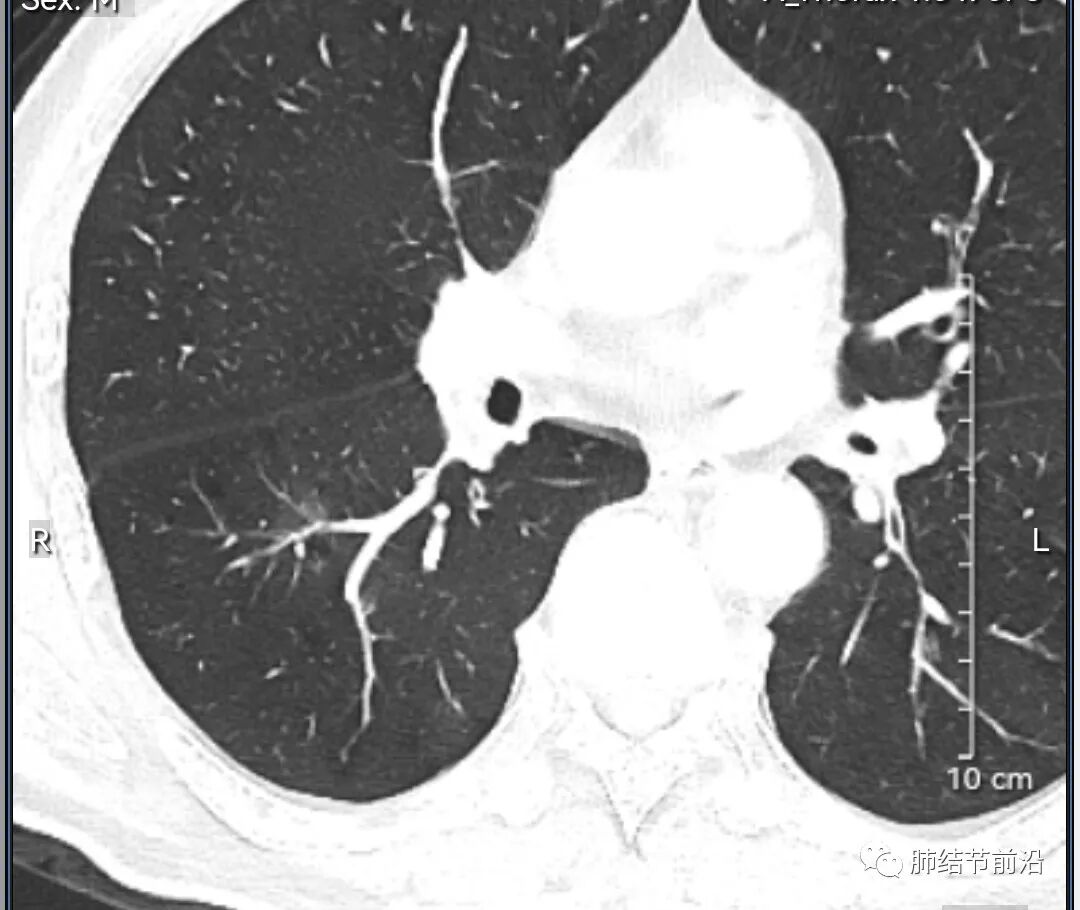

男性,67岁,重度吸烟史。CT发现右下肺囊腔。来看一下这个CT的特点:

该囊腔形态非常有特点,和常见的圆形肺大泡有很大的区别。

1.囊腔中央实性成分,周围有磨玻璃影。

2.囊腔中央有血管。

3.囊腔外周有分叶形态。

4.囊腔有胸膜牵拉。

出现这几种形态,CT可以确认恶性的腺癌。这个囊腔形成的机制,为肿瘤实性成分堵塞细支气管形成活瓣,肺泡内压力增高破裂行成,因此肺内血管成分保留。由于肺泡压力增高,而呈分叶状。另外,也有肿瘤的胸膜牵拉这一特点。

囊腔周围磨玻璃+囊腔中央血管为特征性表现。如果持续存在,几乎可以100%确认为早期肺腺癌。